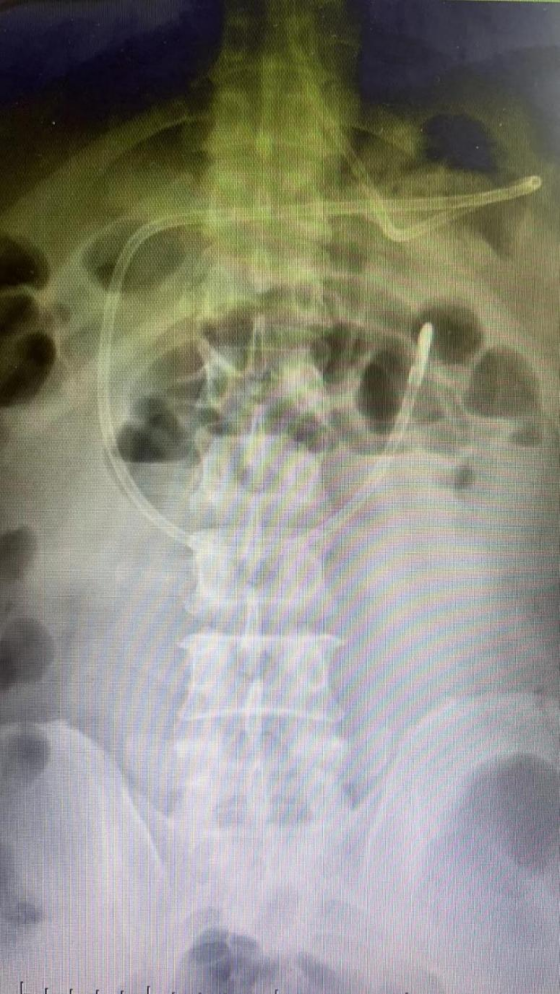

插管后的腹部立位片确认插管位置准确无误视图